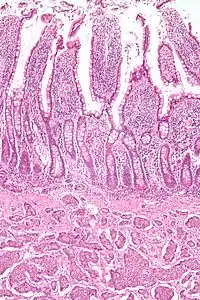

Small intestinal neuroendocrine tumor at bottom third of image, showing the typical intramural (within the wall) location, and overlying intact epithelium. H&E stain

NETs are often small, yellow or tan masses, often located in the submucosa or more deeply intramurally, and they can be very firm due to an accompanying intense desmoplastic reaction. The overlying mucosa may be either intact or ulcerated. Some GEP-NETs invade deeply to involve the mesentery.[69] Histologically, NETs are an example of "small blue cell tumors," showing uniform cells which have a round to oval stippled nucleus and scant, pink granular cytoplasm. The cells may align variously in islands, glands or sheets. High power examination shows bland cytopathology. Electron microscopy can identify secretory granules. There is usually minimal pleomorphism but less commonly there can be anaplasia, mitotic activity, and necrosis.